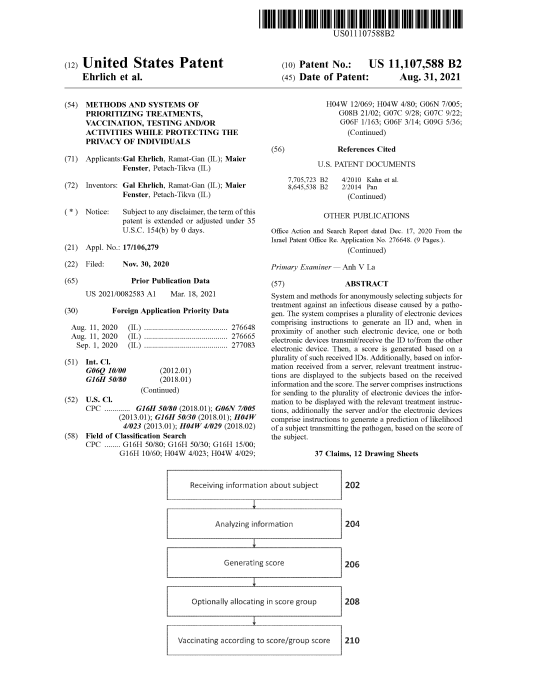

The US Patent 11107588 B2

Please Read MORE about the functionality and pathology of the mRNA lipid graphene and ferric oxide and aluminum nanoparticles so-called vaxxxine by reading the US patent 11107588 B2, before reading the horrific sections in this patent that talk about the AI Alien Parasites.

The following is Section 28 taken from US patent 11107588 B2 talking about the COVID-19 VAXXXines and all COVID-19 preventative treatments can also contain a microorganism in a weakened or live state, a microorganism such as an Artificial Intelligent (AI) parasite (mRNA directed lipid hydrogel containing magnetic graphene ferric oxide and aluminum nanoparticles).

US Patent 11107588 B2 – For Graphenated VAXXXines!